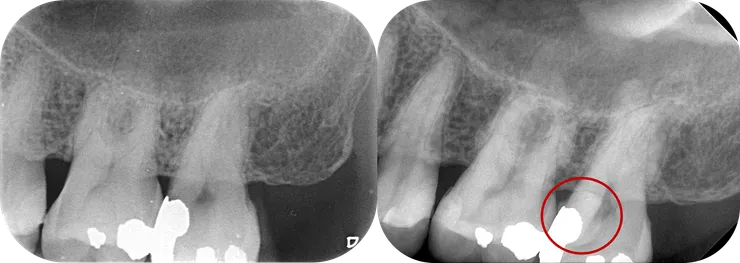

27 with S-curved DB canal